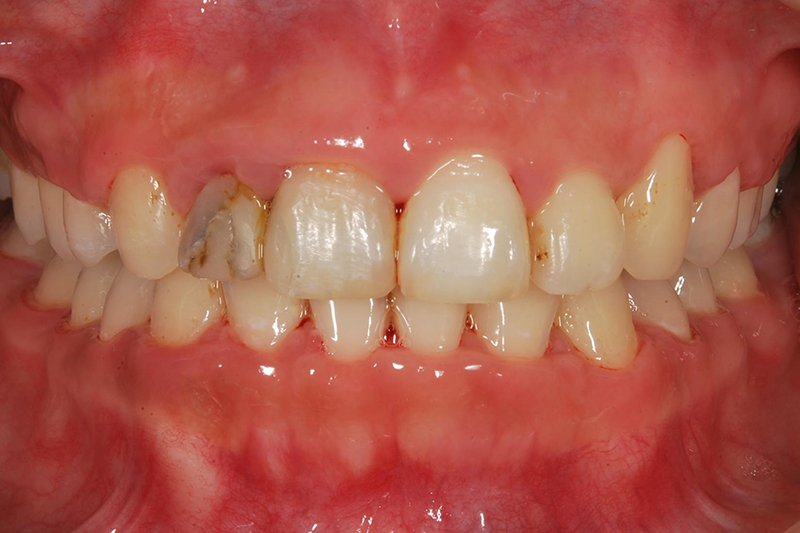

齒列不整

矯正前